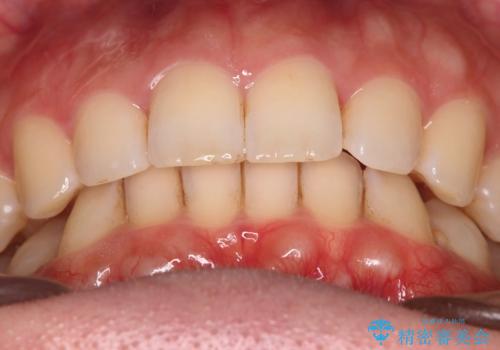

噛み合わせをよくするために、ワイヤー矯正とインビザライン矯正のどちらの期間も必要な箇所にゴム掛けを行いながら治療を行いました。

ゴム掛けを頑張っていただいたので、噛みあわせも改善され綺麗な歯並びになりました。